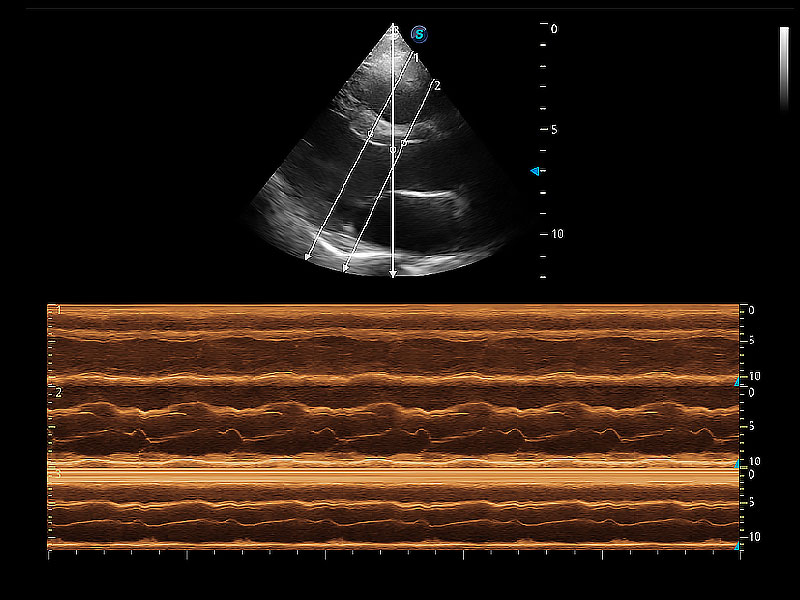

通過360度任意調(diào)節(jié)3條M型取樣線,在同一心動周期上觀察心臟不同位置的運(yùn)動曲線,得到準(zhǔn)確的心功能測量數(shù)據(jù),有效評估心肌運(yùn)動及左心室功能。